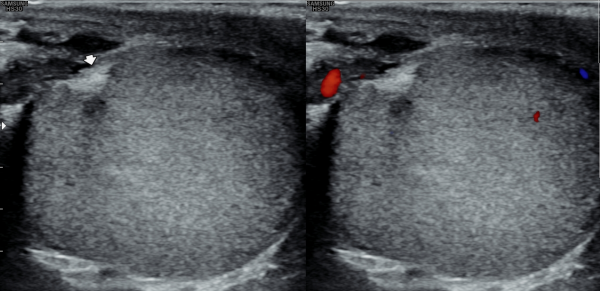

5년뒤 바쁜 일상 생활로 전립선의 관리를 하지 못하고 고환의 통증과 빈뇨 그리고 회음부 통증이 심해진다고 내원 당일 검사한 경직장 전립선 초음파 검사상 사정관 낭종과 낭종내 미세 결석이 생기고 사정관이 탈락된 상피 세포가 70%가량 좁아지고 전립선관도 순환 장애로 전립선 낭종이 관찰되는 초음파 사진입니다.

This transrectal prostate ultrasound image was taken on the day of the visit, five years later. Due to a busy lifestyle, the patient was unable to maintain prostate care and began experiencing worsening testicular pain, frequent urination, and perineal discomfort. The scan shows an ejaculatory duct cyst with microcalcifications inside, as well as narrowing of about 70% of the duct caused by accumulated epithelial cells. Circulatory issues have also led to the formation of prostatic cysts in the prostatic ducts.